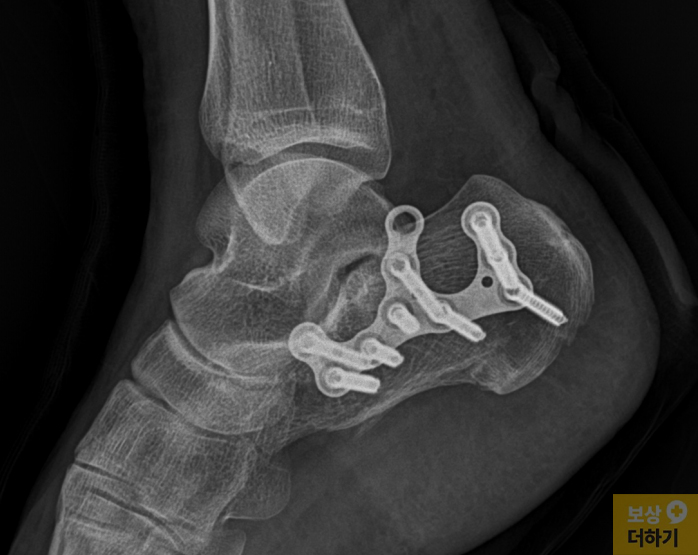

주치의 선생님의 권유로 곧바로 수술을 진행할 수 있었습니다. 무너진 뼈를 맞추기 위해 금속판과 나사못을 박는 큰 수술을 받으셨고, 약 8주간의 고정 치료와 긴 재활 기간이 이어졌습니다. 하지만 수술이 잘 끝났음에도 불구하고, 발목을 안팎으로 움직이거나 위아래로 꺾는 동작이 예전처럼 부드럽지 않았습니다.